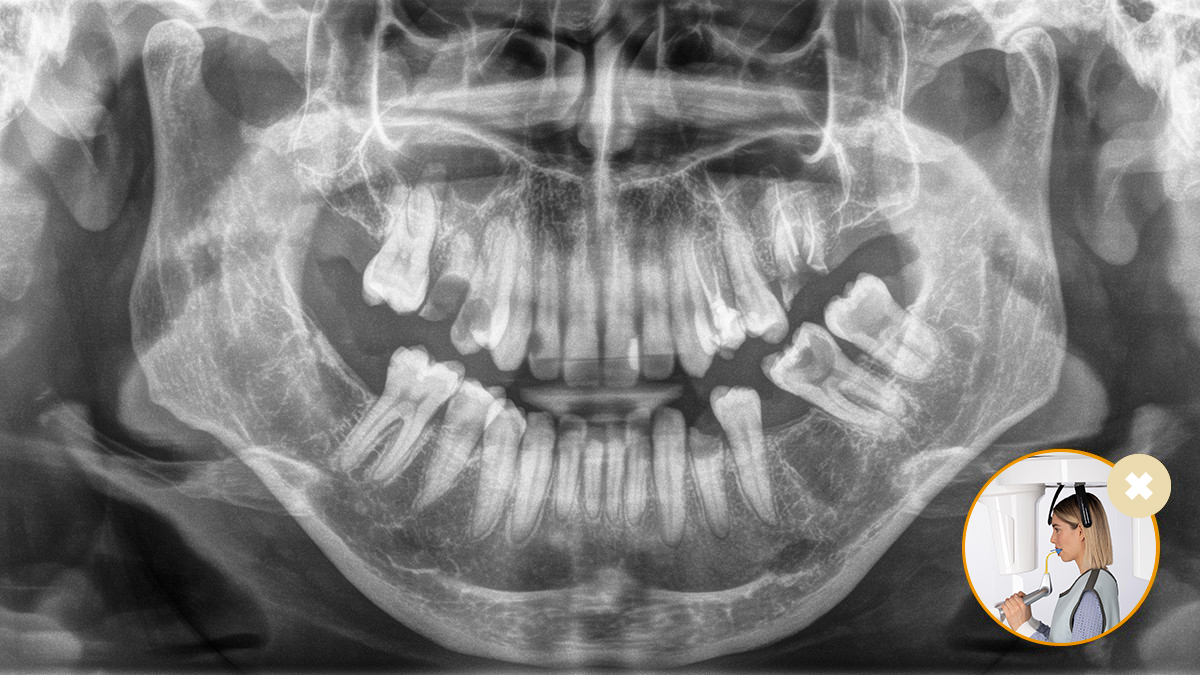

O posicionamento correto do paciente leva à alta qualidade da imagem para apoiar um diagnóstico preciso e facilita e melhora a experiência do paciente.

3. O posicionador automático exclusivo determina automaticamente a inclinação correta da cabeça

7. Compensação automática da coluna vertebral para melhorar a qualidade da imagem panorâmica na região anterior